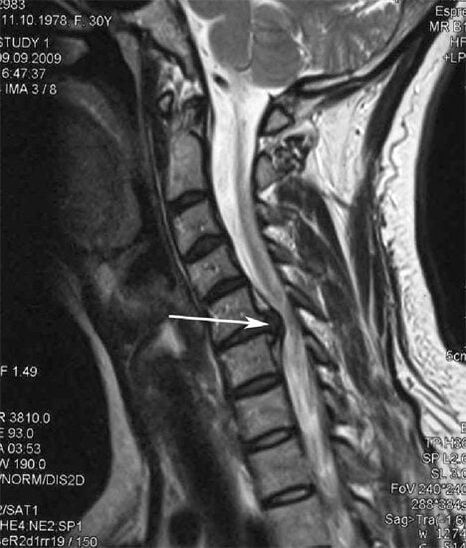

A kezdeti szakaszban az osteochondrosis kimutatása MRI segítségével történik. Később a patológiát radiográfia segítségével lehet diagnosztizálni. A nyaki gerinc röntgenfelvételein észrevehetővé válik a csigolyák közötti távolság csökkenése, a fazett ízületek patológiás változásai és az osteophytosis.